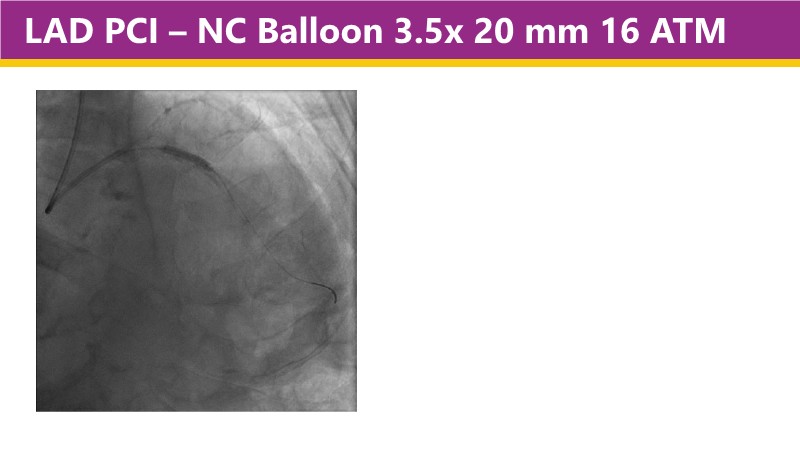

This EuroPCR 2025 session shares real-world insights confirming the promising results of the PINNACLE I trial, with LithiX IVL proving safe and effective across eccentric, concentric, and nodular calcifications.

Learn how this technology works, review the supporting evidence, and follow step-by-step case examples demonstrating optimal stent expansion and an efficient calcium modification workflow in daily practice.